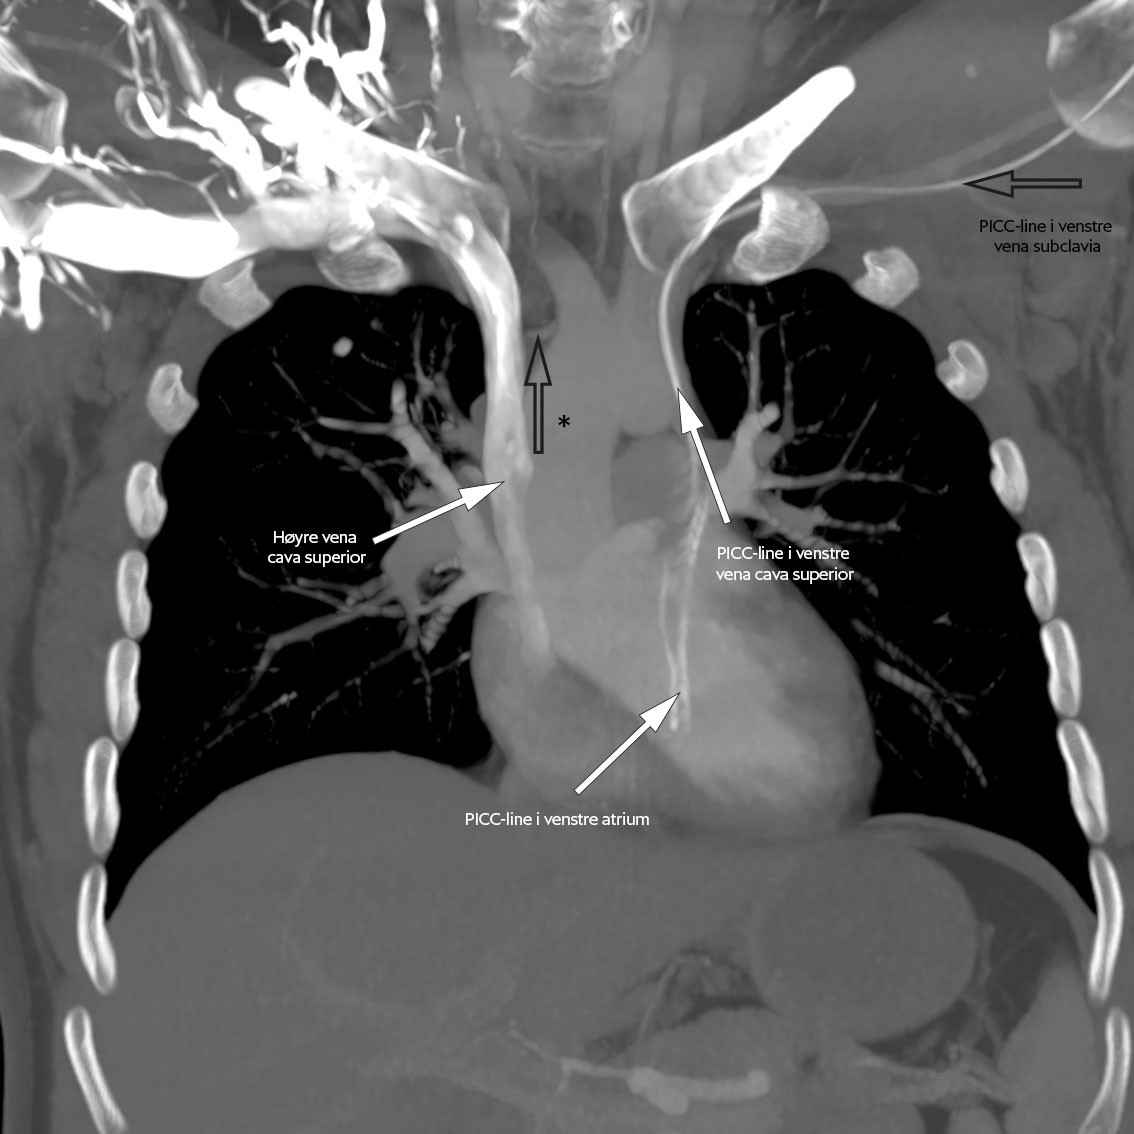

Ved lokalsykehuset var respirasjonen ubesværet, blodtrykket 130/75 mmHg, pulsen 95 slag/min og temperaturen på 39,3 °C. Han var lyssky og nakkestiv. Glasgow Coma Scale (GCS)-skår var 14 med lukkede øyne på grunn av lysskyhet. Blodprøvene viste leukocytter 11,9 × 109/L (referanseområde 3,5–10,0 × 109/L), nøytrofile granulocytter 9,6 × 109/L (1,5–7,3 × 109/L) og CRP 24 mg/L (< 4). Arteriell blodgass uten oksygentilskudd viste hypoksemi med pO2 8,1 kPa (11,0–14,0), men det ble ikke utredet videre pga. hastesituasjon. Blodkulturer og nasofarynksbakteriologi var begge uten senere oppvekst, og han var negativ for pneumokokkantigen i urin. Det ble ikke tatt røntgen toraks. På bakgrunn av sykehistorie med tidligere hjerneabscess ble det gjort CT caput før planlagt spinalpunksjon. CT-undersøkelsen viste en kontrastladende lesjon i høyre temporallapp og tegn på ødem og økt intrakranialt trykk. Intravenøs cefotaksim 3 g × 4 og intravenøs metronidazol 1,5 g × 1 ble igangsatt på mistanke om hjerneabscess, og han ble ikke spinalpunktert. Han ble raskt overflyttet til nevrokirurgisk avdeling ved et universitetssykehus. MR caput samme kveld viste en kontrastladende lesjon med perifokalt ødem i høyre temporallapp (figur 1).

MR caput med kontrast er nødvendig for å stille diagnosen, da det skiller abscess fra andre tilstander som malign tumor, men i praksis vil CT caput ofte tas først (4). Lesjonen framstår på CT som ringformet med kontrastopptak rundt (5). På MR caput med kontrast finner man diffusjonsrestriksjon på diffusjonsvektede sekvenser (diffusion weighted imaging, DWI) og en indre hyperintens og ytre hypointens kant på susceptibilitetsvektede MR-bilder (SWI-magnitude) (6).

MR caput med intravenøs kontrast bekreftet funnet (figur 6). Han ble reoperert dagen etter i narkose med rekraniotomi og fjerning av abscess med kapsel. Pasienten kom seg raskt etter operasjonen uten nevrologiske utfall.